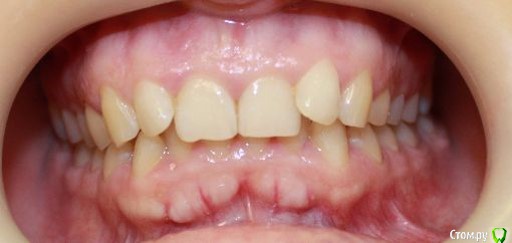

kapyulia Опубликовано 22 декабря, 2017 Поделиться Опубликовано 22 декабря, 2017 Добрый день! Могли бы Вы подсказать есть ли необходимость в удалении зубов (пятерки) с верхней челюсти? Спасибо за помощь. Ссылка на комментарий

Brigita Опубликовано 24 декабря, 2017 Поделиться Опубликовано 24 декабря, 2017 Сложно сказать без очного осмотра, по фото показаний нет. Ссылка на комментарий